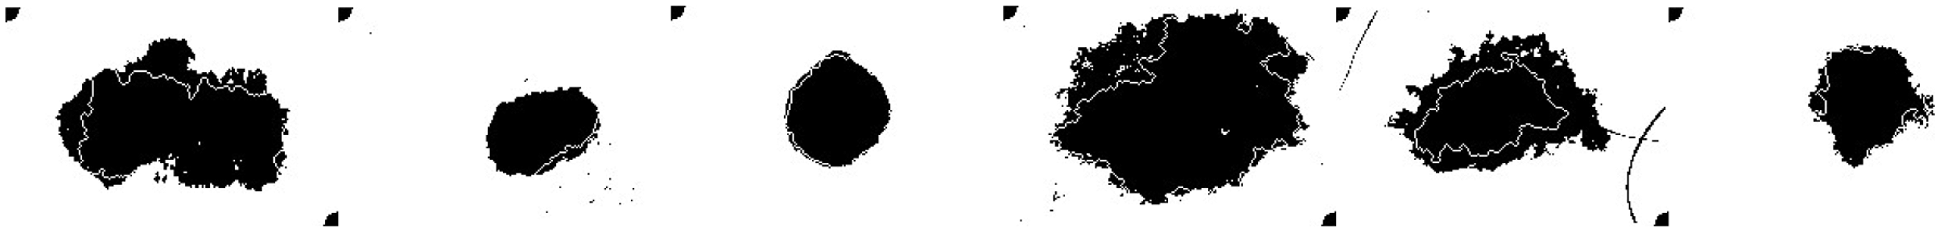

Using LBPCNN and above mentioned preprocessing steps we achieved plausible results. We visually analyzed the separation and region-growing performance of the proposed LBPCNN, Figs. 7 and 8 presents an example of classification results. The white irregular line represents the segmentation of lesions in fair skins. We have cropped the original skin lesion dataset and resized it into 128128 for training and validation/testing. We adopted mirror and rotation operations to enlarge and× get the maximum results from the dataset. We have used local binary pattern (finding rotational invariance using the Eq. (10)) with convolutional neural network (LBPCNN) and then contour of those pixels to get the category of a lesion. LBPCNN has 17 layers (Convolutional layers with Rectified Linear Units, max pooling layers [38] (2 × 2), Dropout layer and Batch Normalization layers) including fully connected layer with stride one and padding value is zero (‘SAME’). We have set the batch size of 50 and trained our neural network with the most successful classifier ADAM [39]. Overfitting problem is catered by dropout [40] layer with a factor of 0.2 and 0.5. The ReLu layer is used to vanish gradient problems in convolutional layers.

Figure 7: Systematically visualize the feature map of our proposed model LBPCNN. The idea behind the visualization of a feature map is what important features are to be highlighted during training for classification detection of cancer